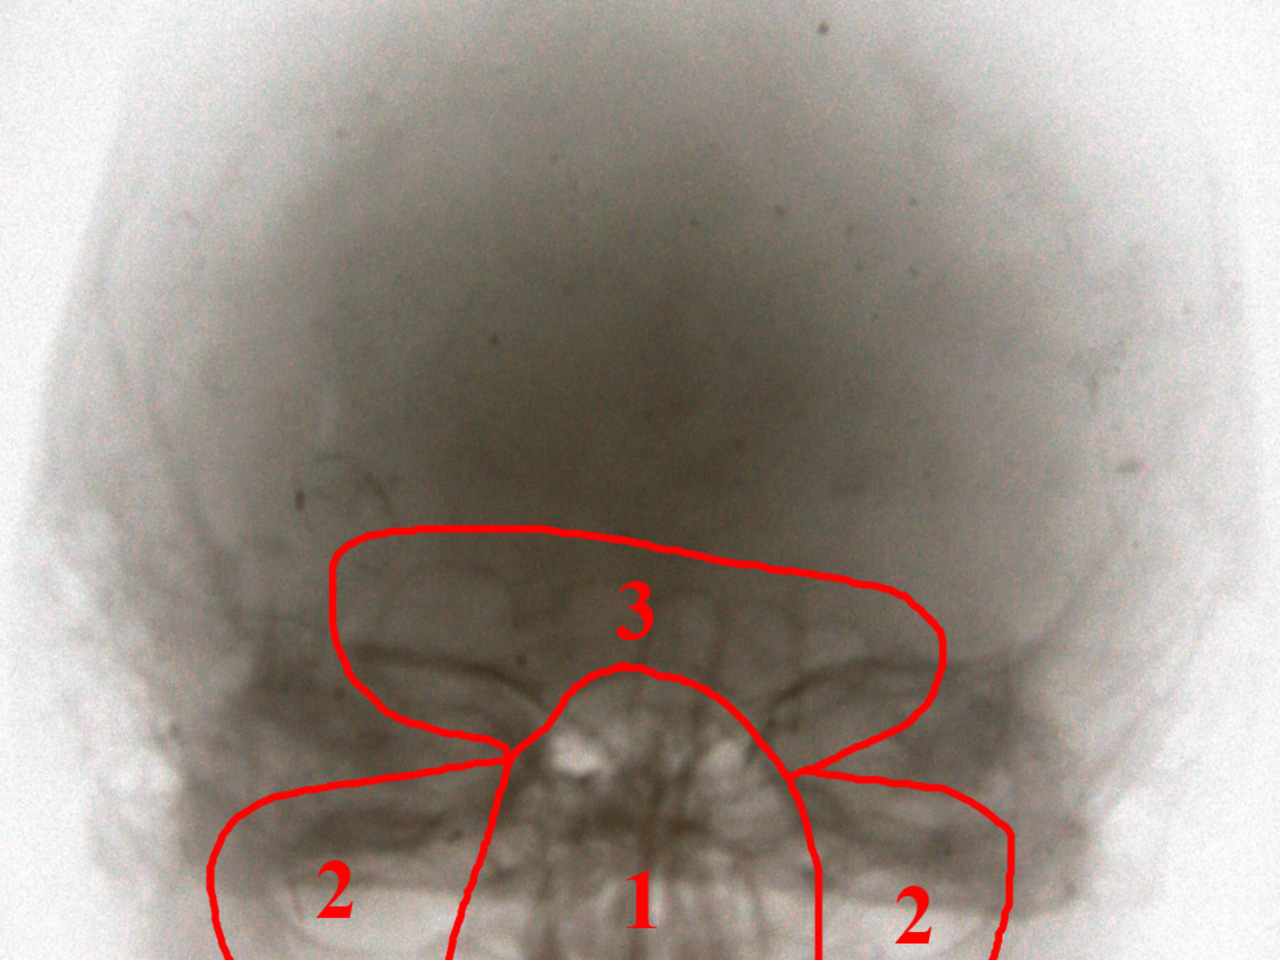

Для примера, рентгеновские снимки моей головы в 18 лет. Череп находился лишь на стадии формирования, и сейчас эти полости в 3-4 раза больше.

1 – Решетчатый лабиринт и клиновидная пазуха. Уходит вглубь головы наполовину.

2 – Гайморовы пазухи. Чаще всего полость носа начинает гнить именно с зубов верхней челюсти.

3 – Лобные пазухи. Их воспаление иногда вызывает боль в области лба и бровей.